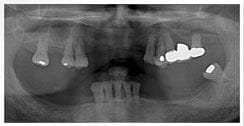

X 光片

術前X光片

術後X光片